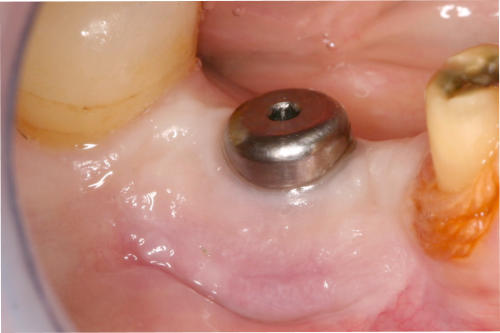

Durch Transplantate kann verlorenes Gewebe wieder aufgebaut werden. Damit wird eine dauerhafte Stabilität der Gewebe und damit auch des Knochens erzielt und eine gute Putzfähigkeit für Zähne oder Implantate erreicht. Beispiele: